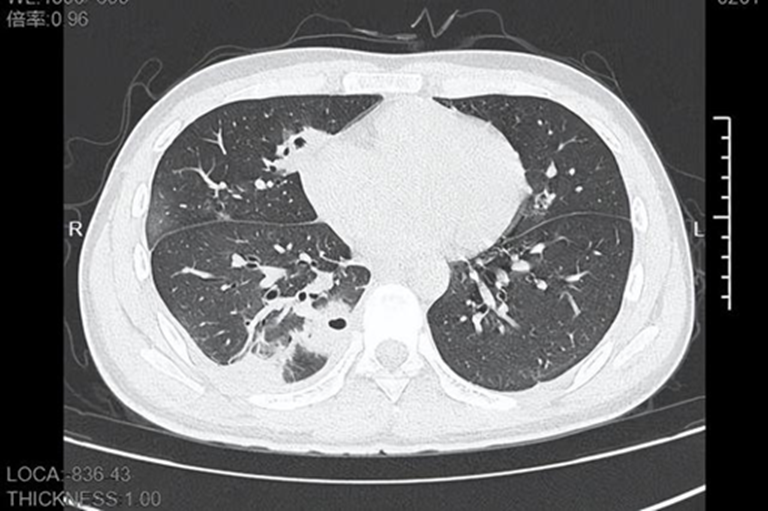

Khi tới bệnh viện, thân nhiệt Lâm đã chạm 39 độ C. CT ngực cho thấy bên trong phổi xuất hiện hơn 10 hốc rỗng , một số vùng mô phổi đã hoại tử, biểu hiện điển hình của áp-xe phổi do vi khuẩn từ đường máu .

Xét nghiệm cho thấy thủ phạm là tụ cầu vàng (Staphylococcus aureus), loại vi khuẩn sống ngay trên bề mặt da của hầu hết mọi người.